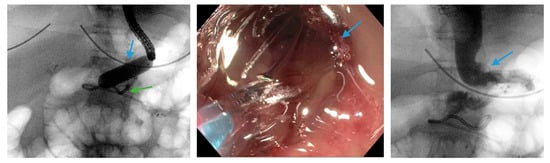

Figure 1.

Upper gastrointestinal series reveals a 23 mm × 15 cm fully-covered esophageal self-expanding metal stent from the distal esophagus to the mid portion of the sleeve anchored by two through-the-scope clips (blue arrows) and one over-the-scope clip (green arrow) placed on the proximal edge of the stent.

Scheme 6.

Upper endoscopy reveals the proximal (blue arrows, left) and distal edge (blue arrows, middle) of a fully-covered esophageal self-expanding metal stent anchored by two through-the-scope clips (blue arrows, right) and an over-the-scope clip (green arrows, right). Note copious saliva collected around the non-peristaltic prosthesis.